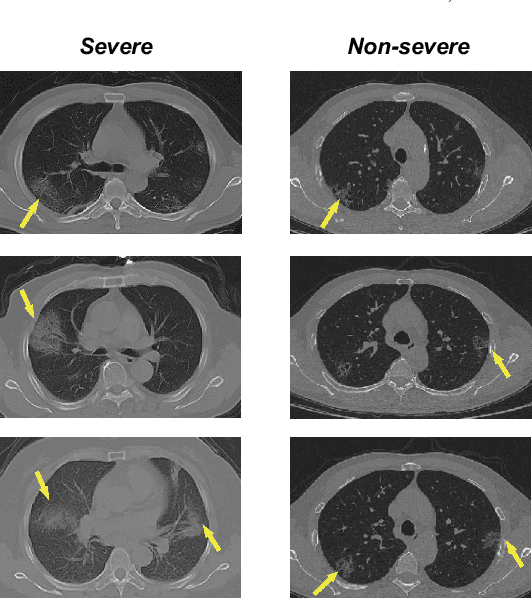

Abstract:How to fast and accurately assess the severity level of COVID-19 is an essential problem, when millions of people are suffering from the pandemic around the world. Currently, the chest CT is regarded as a popular and informative imaging tool for COVID-19 diagnosis. However, we observe that there are two issues -- weak annotation and insufficient data that may obstruct automatic COVID-19 severity assessment with CT images. To address these challenges, we propose a novel three-component method, i.e., 1) a deep multiple instance learning component with instance-level attention to jointly classify the bag and also weigh the instances, 2) a bag-level data augmentation component to generate virtual bags by reorganizing high confidential instances, and 3) a self-supervised pretext component to aid the learning process. We have systematically evaluated our method on the CT images of 229 COVID-19 cases, including 50 severe and 179 non-severe cases. Our method could obtain an average accuracy of 95.8%, with 93.6% sensitivity and 96.4% specificity, which outperformed previous works.